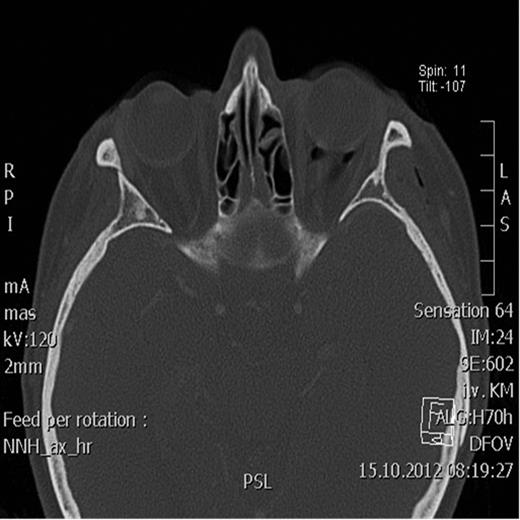

Postoperative axial CT scan showing normal position of the bulbus.

Two days after surgery, the patient was discharged with restored visual acuity and continuing resolution of the left periorbital swelling and proptosis.